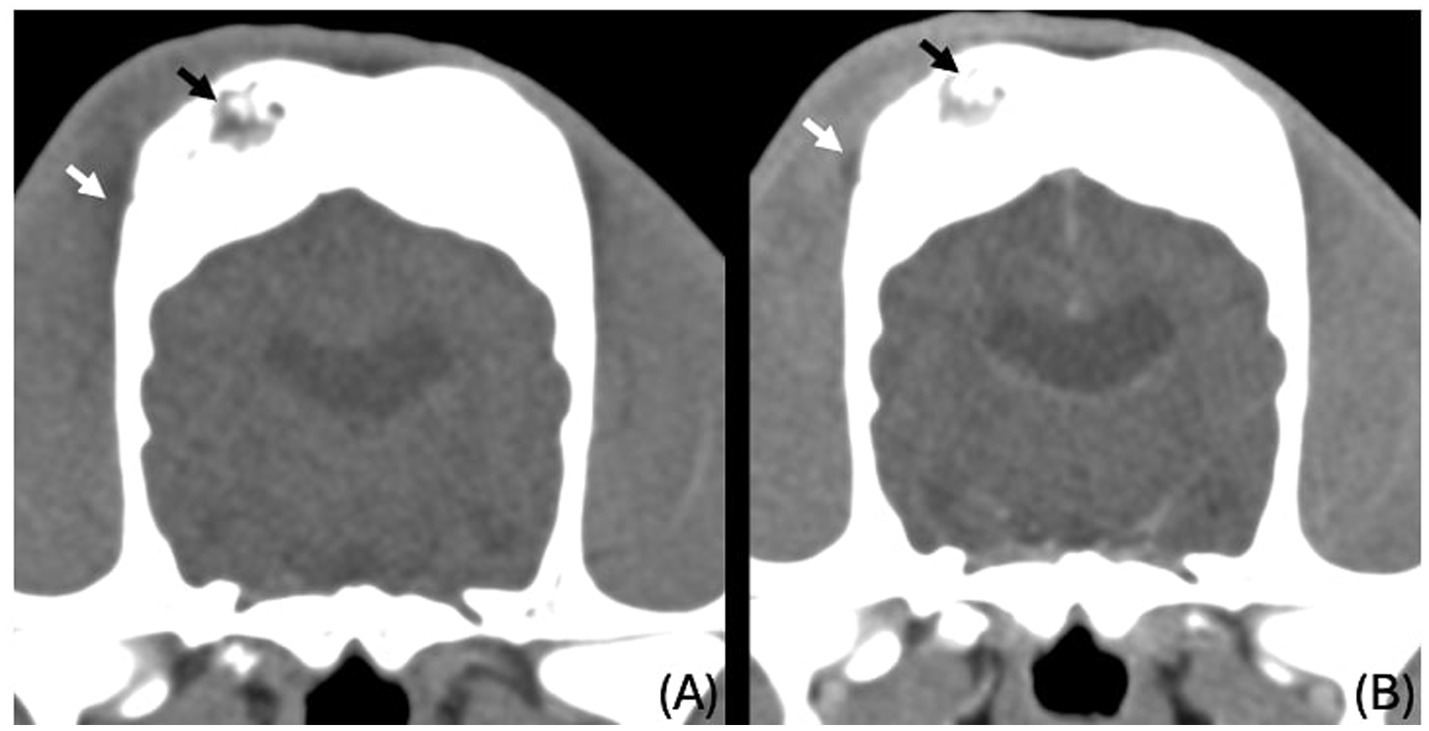

The images revealed severe, bilateral and symmetrical thickening of the parietal, occipital and frontal bones, as well as the squamous part of the left temporal bone (Figure 1, white arrows). The lesions were characterised by prominent bone sclerosis, which appeared lamellated in some areas, as well as more focal irregular areas of hypoattenuation with punctate lysis of the cortex (at the right frontal, left parietal, and left occipital bones) (Figure 2, white arrowheads). The osteopenic areas were occupied by mixed soft tissue and fluid attenuation with patchy contrast enhancement (Figure 3, black arrows). Irregular margination with smooth periosteal reaction of the intracranial side of the occipital and parietal bones was also noted. The os tentorium was thickened and sclerotic, especially on the left side.

Figure 3. Transverse CT images of the parietal bones unenhanced (A) and post contrast venous phase (B), showing the areas of lysis being occupied by fluid to soft tissue attenuating material (black arrows) and ill-defined hypoattenuating, contrast enhancing changes in the right temporal muscle (white arrows).

Subtle, ill-defined areas of hypoattenuation were noted at the right temporal muscle overlying the temporal bone with associated swelling (Figure 3, white arrows). These were more conspicuous on the post-contrast series, as ill-defined contrast enhancement was noted surrounding them. Similar changes were noted on the left temporal muscle in the region of the left occipital bone.